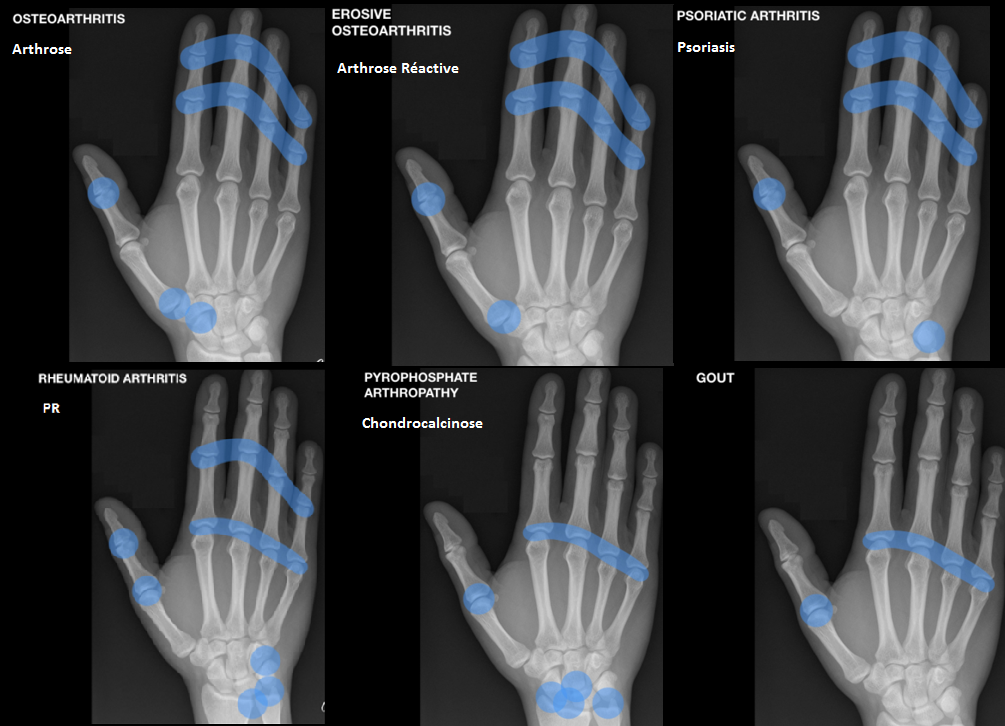

Schema Resumé des mains

poly arthrite rhumatoöde

Rayons atteints = MCP et IPP

Initial

- Erosions marginales (en “coup d’ongle”) du bord radial de la tête des 2e et 3e MCP

- puis des bases phalanges

Evolution

- Pincement

- Erosions

- Deformation en boutonnière (flexion IPP, extension IPD)

- Deformation en col de cygne (extension IPP, flexion IPD)

- Deformation “en coup de vent” cubitale des MCP